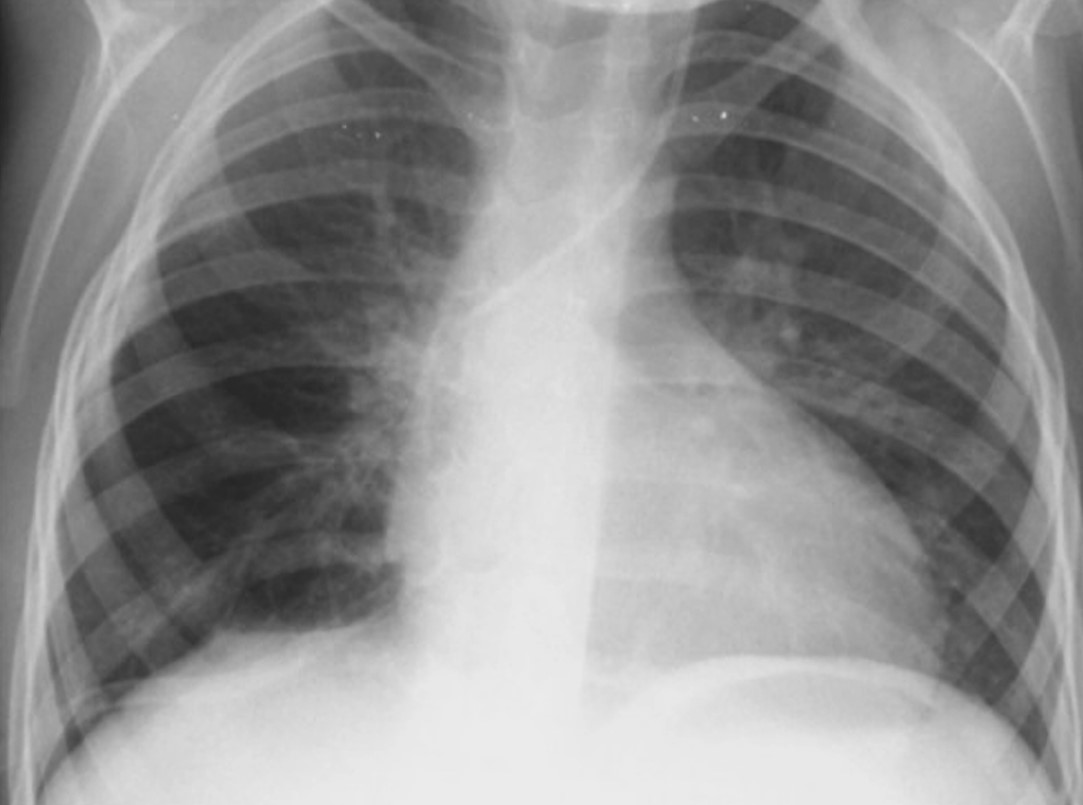

Опухоль размером примерно 12 × 9 × 10 сантиметров занимала около 80% области грудной клетки. Фото Центра детской хирургии им. Н. Георгиу